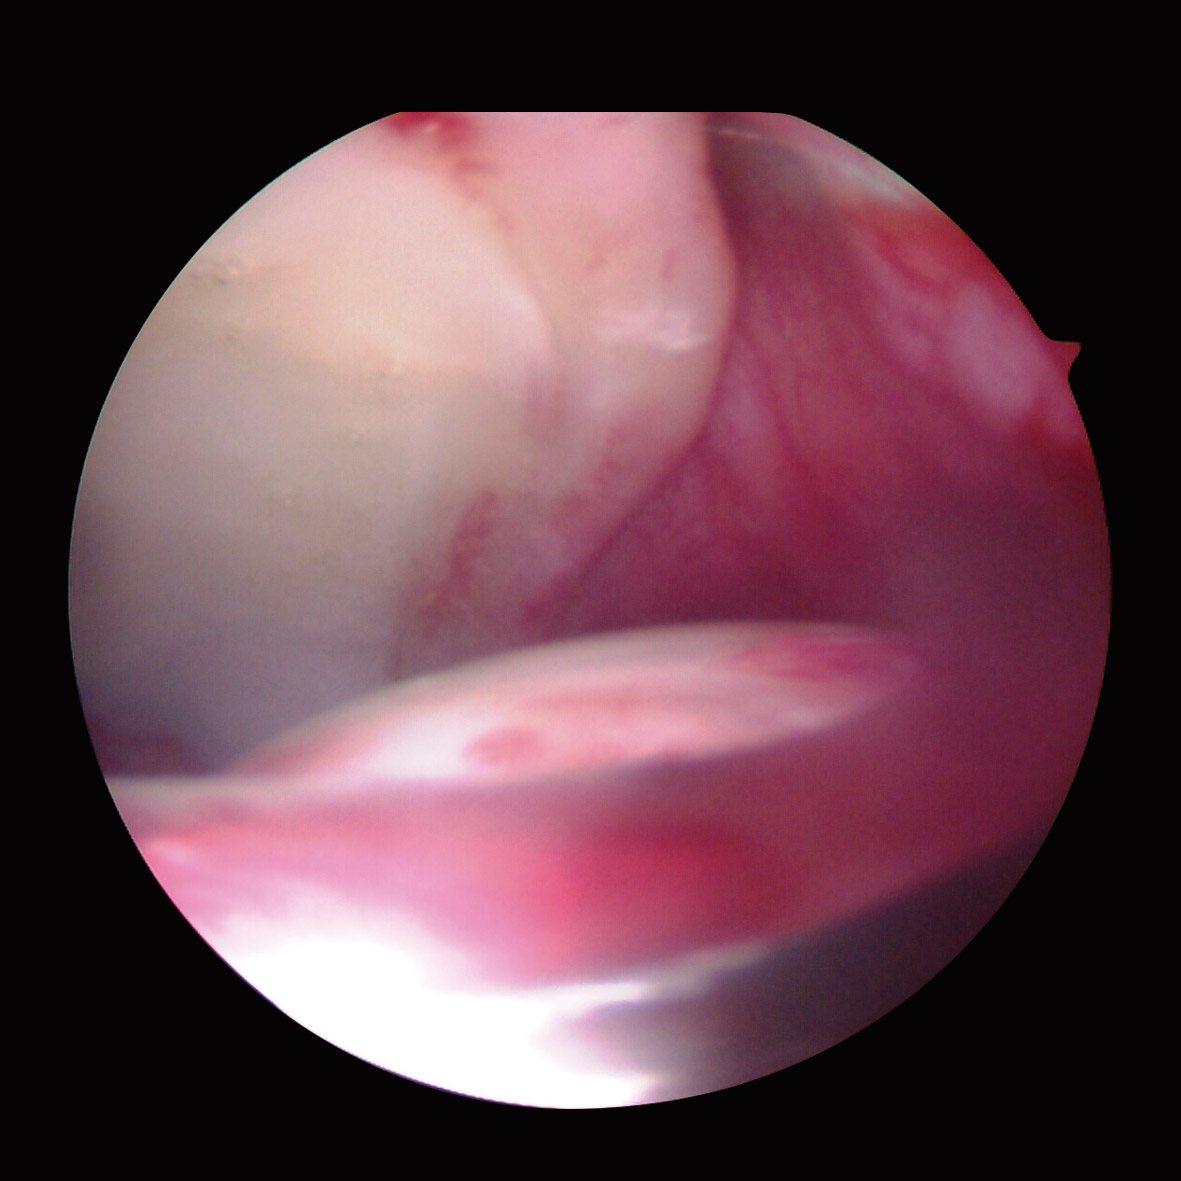

Artroscópicamente, el tipo de CFA era mixto en 86 caderas (52,7%), de tipo Cam en 67 (41,1%) y de tipo Pincer en 10 (6,2%). El labrum presentaba una morfología normal (Figura 1) en 140 caderas (85,9%), hipoplásico (Figura 2) en 17 (9,8%) e hiperplásico (Figura 3) en 6 (4,3%). Se detectó algún grado de rotura del labrum en 133 caderas (81,6%); de ellas, en 98 caderas (60,1%) eran separaciones condrolabrales (Figura 4), en 26 (15,9%) roturas complejas-degenerativas (Figura 5), en 5 (3,0%) roturas parciales y en 4 (2,4%) roturas completas. El labrum presentaba cambios intrasustancia en 30 caderas (18,4%), distinguiendo en 19 (63,3%) calcificado, 9 (30%) hemático (Figura 6) y 2 (6,6%) mucoide-amarillo.

La morfología del labrum normal ha predominado en el CFA mixto y en el CFA de tipo Cam, en un 86 y un 94%, respectivamente. El sobrecrecimiento o “giba” presente en la zona de transición entre la cabeza y el cuello femoral provoca, en los movimientos de flexión y rotación interna de la cadera, una elevación e impacto sobre el labrum, que afecta a la unión condrolabral(1)(5). El labrum hipoplásico se ha presentado en el 41,1% de las caderas con CFA de tipo Pincer. El mecanismo de choque de tipo “contrafuerte” entre el cuello femoral y el labrum provoca un aplastamiento continuado del labrum acetabular que causa la degeneración y la hipoplasia(1)(4) y el labrum hiperplásico ha predominado en CFA de tipo Cam con valoración radiológica indicativa de déficit de cobertura acetabular, en las que debido a esta falta de contención ósea, las fuerzas de carga actúan directamente sobre el labrum acetabular(27).

La rotura del labrum acetabular se ha presentado en un 79% en el CFA mixto, en un 89,5% en el CFA de tipo Cam y en un 80% en el CFA de tipo Pincer. Su localización más frecuente es la anterosuperior(4)(28), al igual que coincide con los resultados de nuestra serie. La superficie cóncava del acetábulo está más expuesta a las fuerzas de cizallamiento que la cabeza femoral. Y el impacto repetido de la “giba” femoral y el cuello femoral contra el labrum produce una lesión progresiva del mismo.